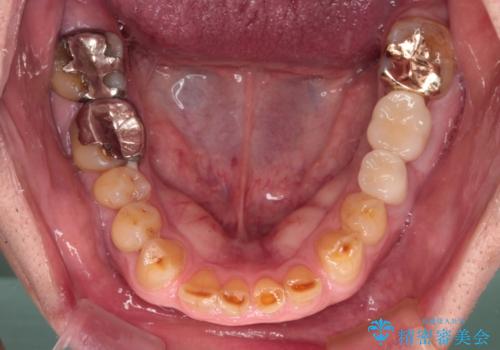

- 上下の奥歯が痛いとのことで来院された患者様です。

診察をしたところ、上下大臼歯の歯肉に排膿路認められたため、根管治療を行い、その後補綴治療を行うこととしました。

また、上顎の欠損部位にはインプラント治療を行うこととしました。

治療を開始したところ、上顎は排膿路が消失し、症状も落ち着きましたが、下顎は一向に改善されませんでした。

改めて診療を行ったところ、歯根破折が認められ、抜歯後にインプラント治療を行うこととしました。